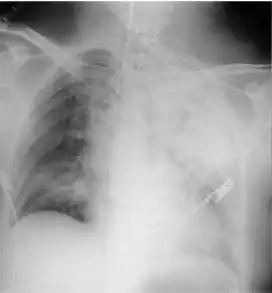

Mendelson's syndrome is characterised by a bronchopulmonary reaction following aspiration of gastric contents during general anaesthesia due to abolition of the laryngeal reflexes. The main clinical features are signs of general hypoxia, two to five hours after anaesthesia. Such features may include cyanosis, dyspnea, fever, pulmonary wheeze, crepitant rales, rhonchi, and tachycardia with a low blood pressure. Decreased arterial oxygen tension is also likely to be evident. Pulmonary edema can cause sudden death or death may occur later from pulmonary complications.

The evaluation of Mendelson syndrome is based on the following:[4]

- Radiographic film